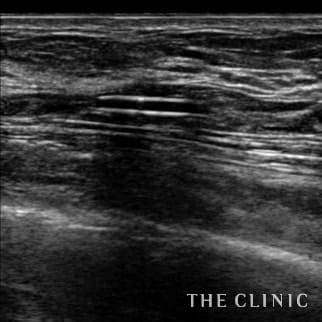

Breast-hip Photo Gallary / No.696

35歳 女性 アクアフィリング(アクアリフト)豊胸のお悩みのアクアフィリング(アクアリフト)豊胸除去

半年前に他院でアクアフィリング豊胸を行いましたが、バストの変形やしこりに悩み除去手術を希望しました。 見た目には右胸内側上部と左胸内側下部に不自然な盛り上がりとしこりを認めました。エコーではアクアフィリングのしこりが散在し、一部は塊になっていました。 アクアフィリングは生理食塩水で溶解されますが、完全には溶解せず固まっていますので、吸引して除去しました。治療の概要 アクアフィリング除去+コンデンスリッチ豊胸:乳腺用エコーを用いて、バスト内の状態を確認。その後、生理食塩水でアクアフィリングを溶解する。溶解仕切れない場合には、注射器で吸い出し除去。アクアフィリング の除去後、バストの皮下にコンデンスリッチファット(老化細胞や不純物を取り除いて濃縮させた自己脂肪)を注入。 施術費用 アクアフィリング 除去(会員料金):¥600,000(税込¥660,000)/溶解1部位

コンデンスリッチ豊胸(モニター価格):¥880,000〜(税込¥968,000〜)